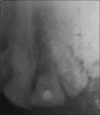

Extracted teeth can be bonded directly to adjacent teeth utilizing a prefabricated composite resin framework reinforced with polyethylene fiber as a noninvasive long-term provisional tooth replacement. This immediate provisional restoration allow for exact repositioning of the coronal part of the extracted tooth in its original intraoral three-dimensional position and thus relieves the apprehension of the patient caused by the sudden loss of an anterior tooth.